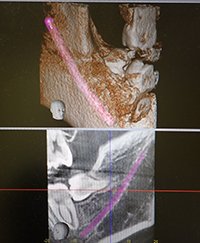

デジタルレントゲン

最新のCTにより正確で、より安全な診断を行う事ができ、治療の確実性を高める事が出来ます。 |